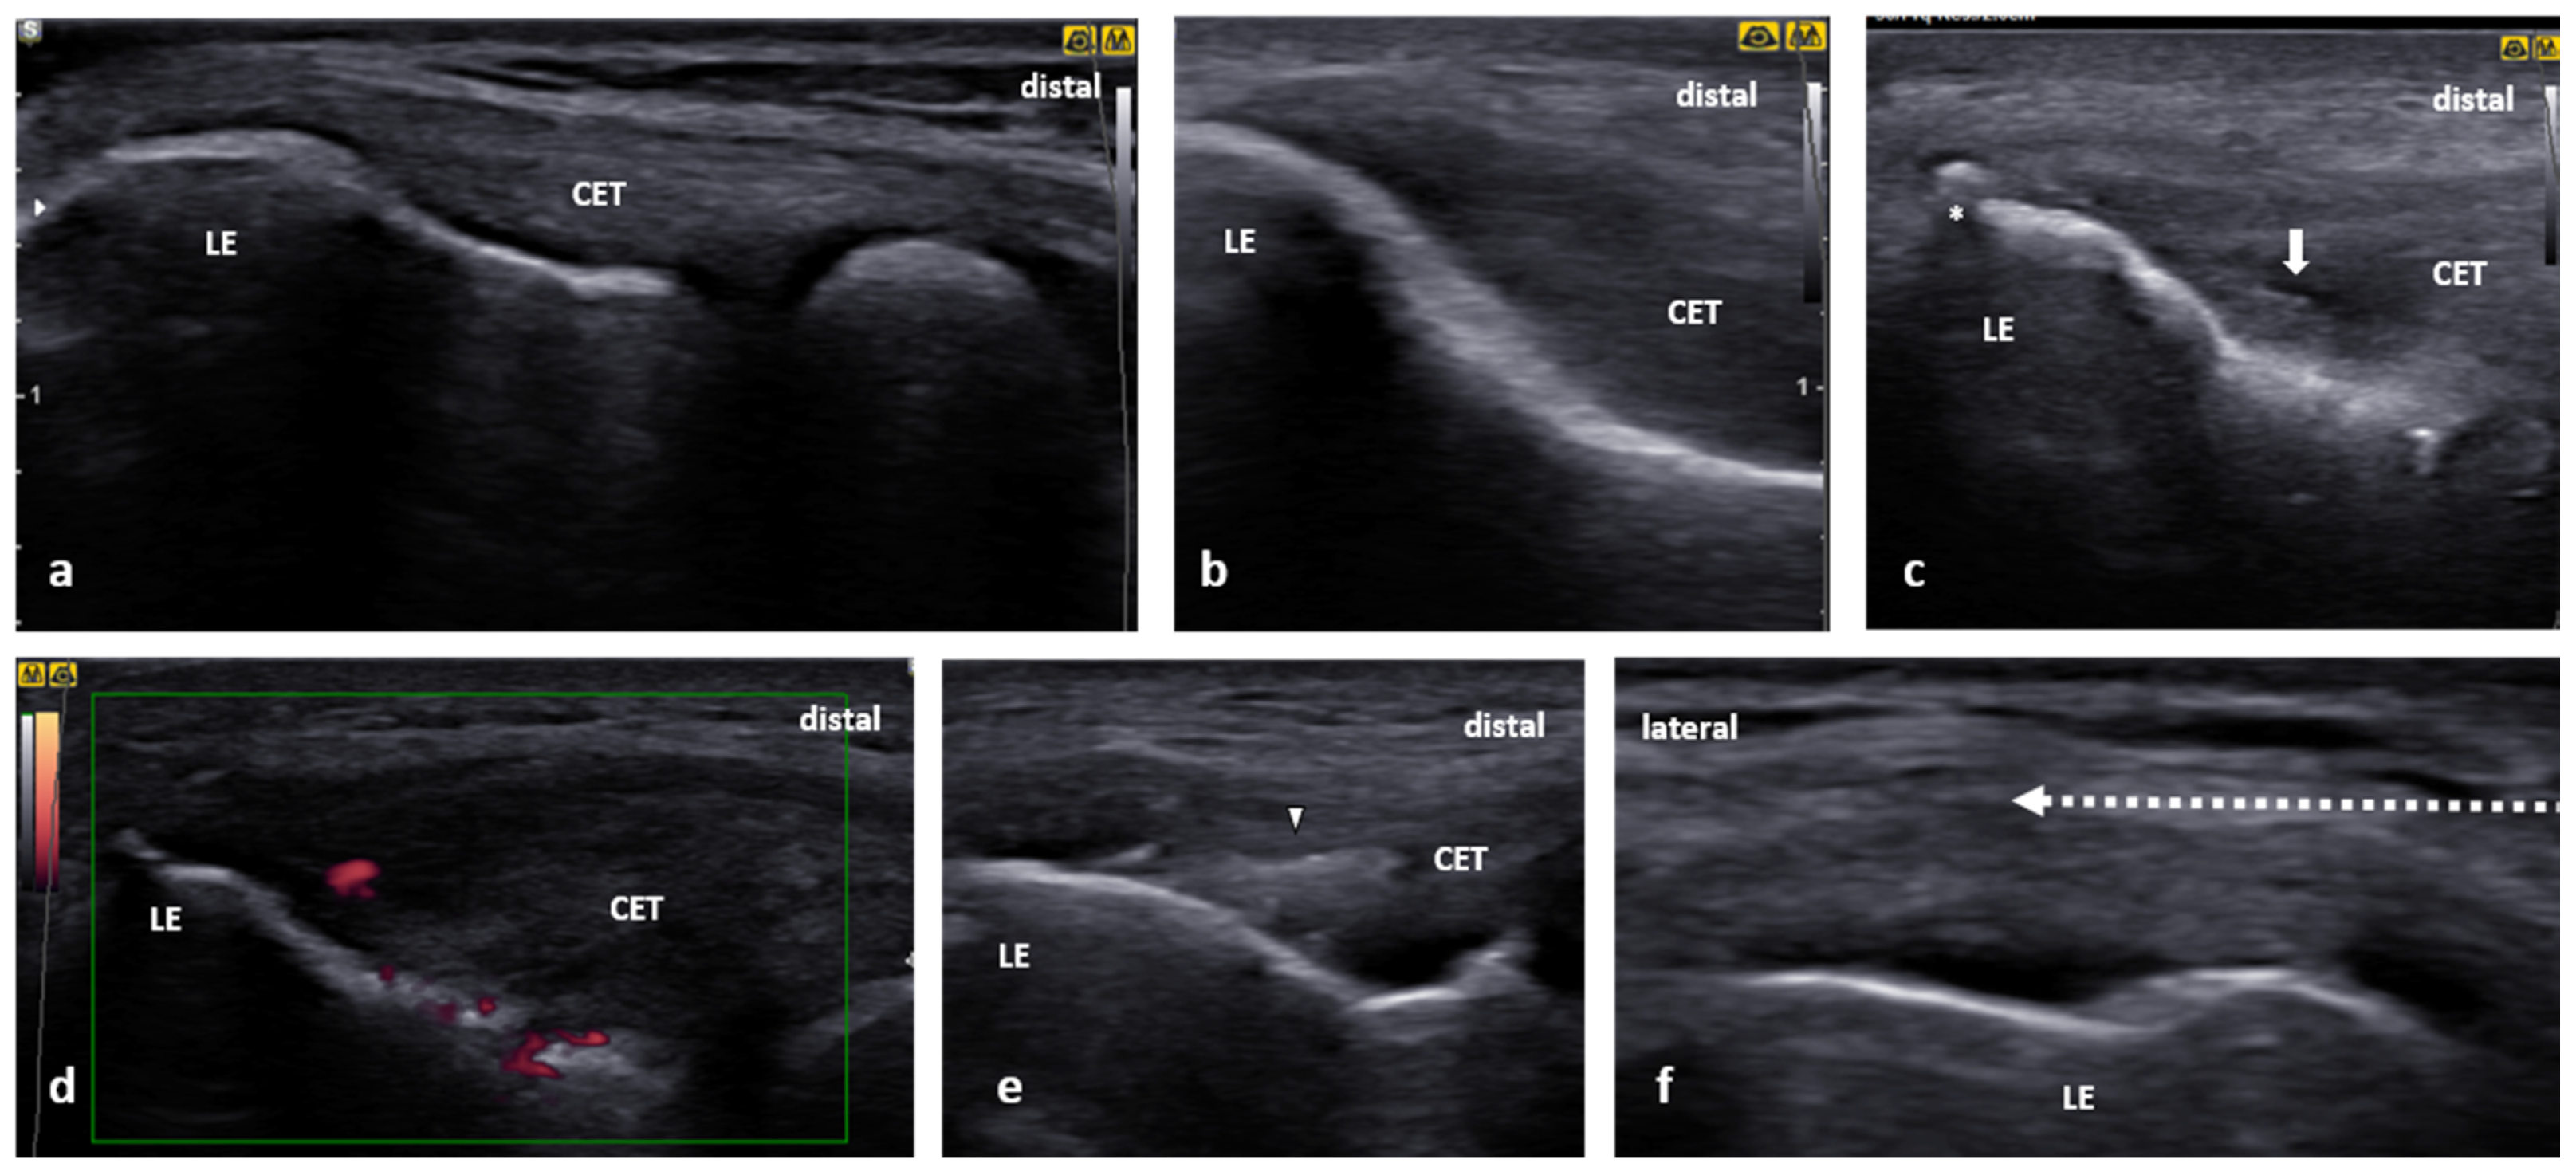

3.1. Tennis Elbow

3.1.2. US scanning and Guided Injection